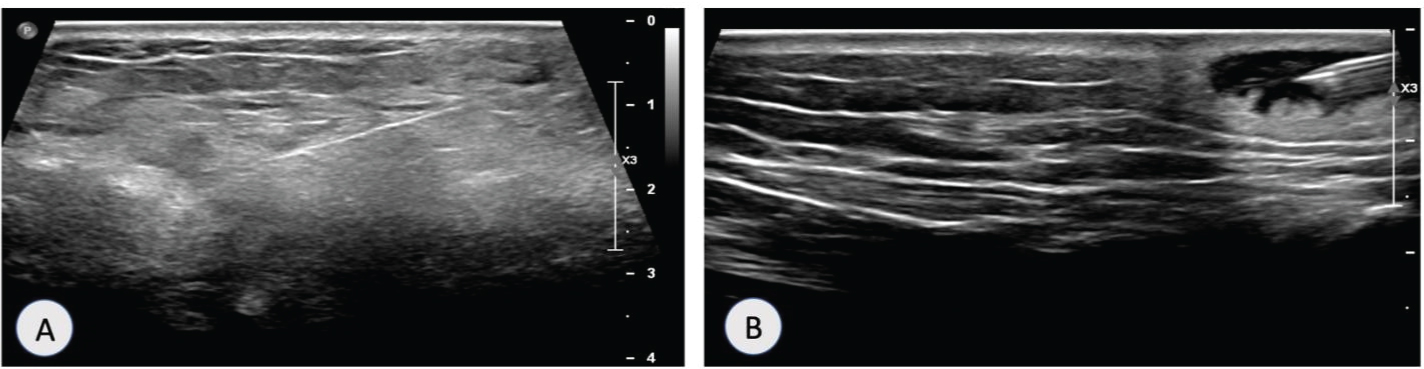

Patient was admitted with suspicion of widespread malignancy and underwent ultrasound guided biopsy of left breast ulcer (Figure 6A), right wrist subcutaneous nodule (Figure 6B), lumbar puncture and arthrocentesis of left knee.

Figure 6: (A) Ultrasound guided biopsy of left breast lesion; (B) Ultrasound guided biopsy of right wrist lesion. View Figure 6